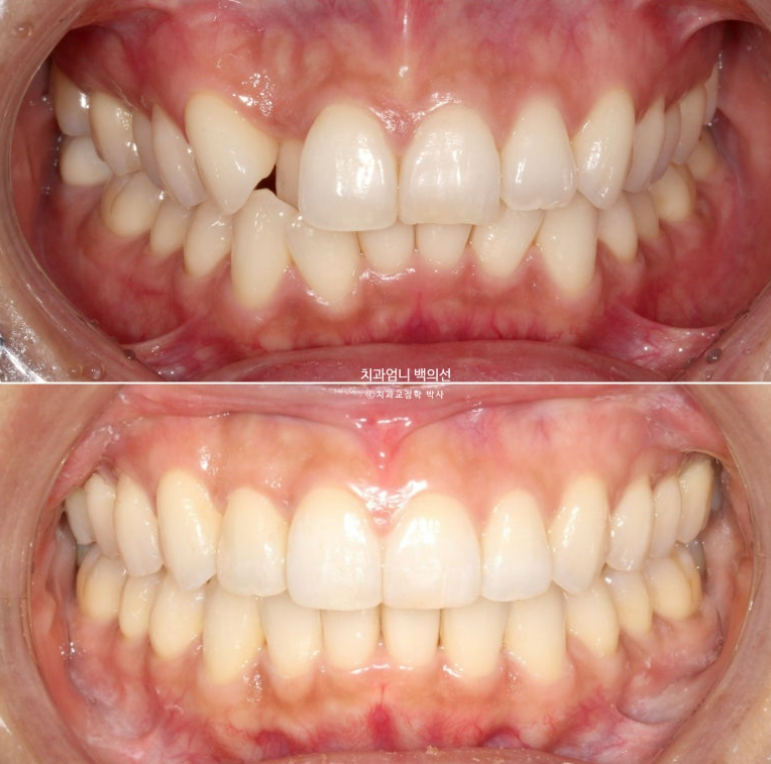

24년 9월부터 25년 1월까지 5개월간 추가장치를 다 낀 모습입니다.

비로소 덧니는 완벽히 제자리를 찾았지만

여전히 약 1mm 가량의 위 아래 중심선 불일치가 보여 환자분 기준 우측 가운데 앞니의 치축이 미세하게 기울어져 보입니다.

환자분도 만족하고 지금도 충분히 좋지만 앞니 중심선을 좀더 일치시키고 치축이 약간 기울어져 보이는 앞니 하나를 위해 2번째 추가장치 제작에 들어갑니다.

25년 2월에서 4월까지 3달간 두번째 추가장치를 모두 끼고 25년 4월에 드디어 치료를 마무리 했습니다.

총 치료기간은 1년 6개월 소요되었고 재제작은 총 2회입니다.

중심선은 잘 맞고 치축이 미세하게 기울어져 보이던 앞니도 개선이 되었습니다

교정치료의 기본은 교합입니다 교합이 좋지 않으면 교정치료를 마무리 짓지 않습니다.

가지런해진 배열과 유지장치 모습입니다.

위 아래 앞니 중심선은 정확히 매치가 됩니다.

덧니는 잘 배열되었습니다.